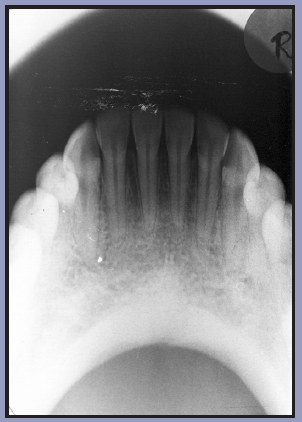

Figure 64 shows the palate (roof of the mouth), zygomatic process of the maxilla (a projection from the maxilla), antero-inferior aspects of each antrum (in this case, the maxillary sinuses), nasolacrimal canals (tear ducts), teeth from the left second molars to the central incisors, and the nasal septum (cartilage dividing the nose).

Uses: To view the maxilla for anterior alveolar fractures, cysts, supernumerary teeth, and impacted canines, and to view pathology at the apices of the incisors. It is not used to diagnose periodontal conditions.

Patient positioning: The patient is seated with the sagittal plane perpendicular to the floor and the occlusal plane parallel to the floor. Before any radiographic images are exposed, the patient must be draped with a protective apron and thyroid collar. The apron must be properly placed to avoid interference with the radiographic exposure.

Receptor placement: Use a type 4 receptor. With the tube side of the receptor toward the maxilla, the receptor is placed crosswise in the mouth, like a cracker. It is gently pushed backwards until it contacts the anterior border of the mandibular ramus. The patient bites down gently to maintain position.

Exposure factors: Follow the recommendations of the receptor and equipment manufacturer.

Direction of the central ray: The central ray is directed at the center of the receptor with a vertical angulation of +65 degrees and a horizontal angulation of 0 degrees. In this case, the central ray will pass through the bridge of the nose, as in Figure 65.